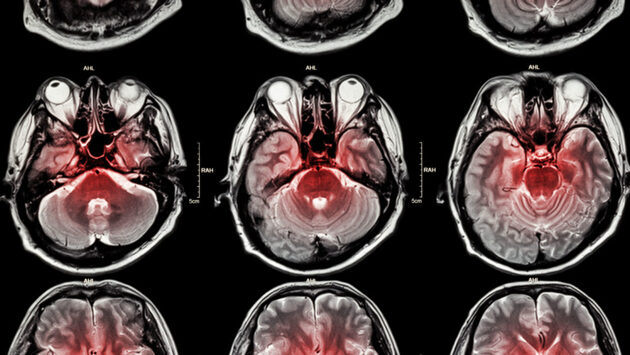

Триглицериды, сахар в крови, вес и объём талии: какие факторы влияют на риск инсульта

Инсульт - основная причина смерти во всём мире, а в последние годы это состояние стало встречаться чаще. В рамках новой научной работы исследователи выяснили, связан ли индекс здоровья TyG-WWI с риском возникновения инсульта среди населения в целом.

В ходе нового исследования учёные проанализировали данные NHANES с 1999 по 2018 год. Сосредоточились они на взрослых. Основное внимание эксперты уделяли индексу TyG-WWI. Он объединяет уровень триглицеридов, уровень сахара в крови, массу тела и объём талии для оценки рисков для здоровья. Также специалисты взяли у участников образцы крови и измерили параметры тела.

Было обнаружено, что по мере увеличения значений TyG-WWI увеличивался и риск возникновения инсульта. После учёта всех факторов рост показателей TyG-WWI оказался связан с повышением вероятности столкнуться с инсультом на 15%.

Также исследователи разделили всех участников на четыре группы в зависимости от значений TyG-WWI. В сравнении с группой с самыми низкими параметрами в других группах риск возникновения инсульта был выше: на 38% по сравнению с людьми с самыми высокими показателями и на 37% по сравнению с теми, кто имели вторые по величине значения TyG-WWI. Это значит, что более высокие показатели триглицеридов, сахара в крови, массы тела и объёма тали связаны с большими шансами на инсульт. При этом зависимость была линейной: по мере увеличения значений TyG-WWI увеличивался и риск возникновения инсульта.